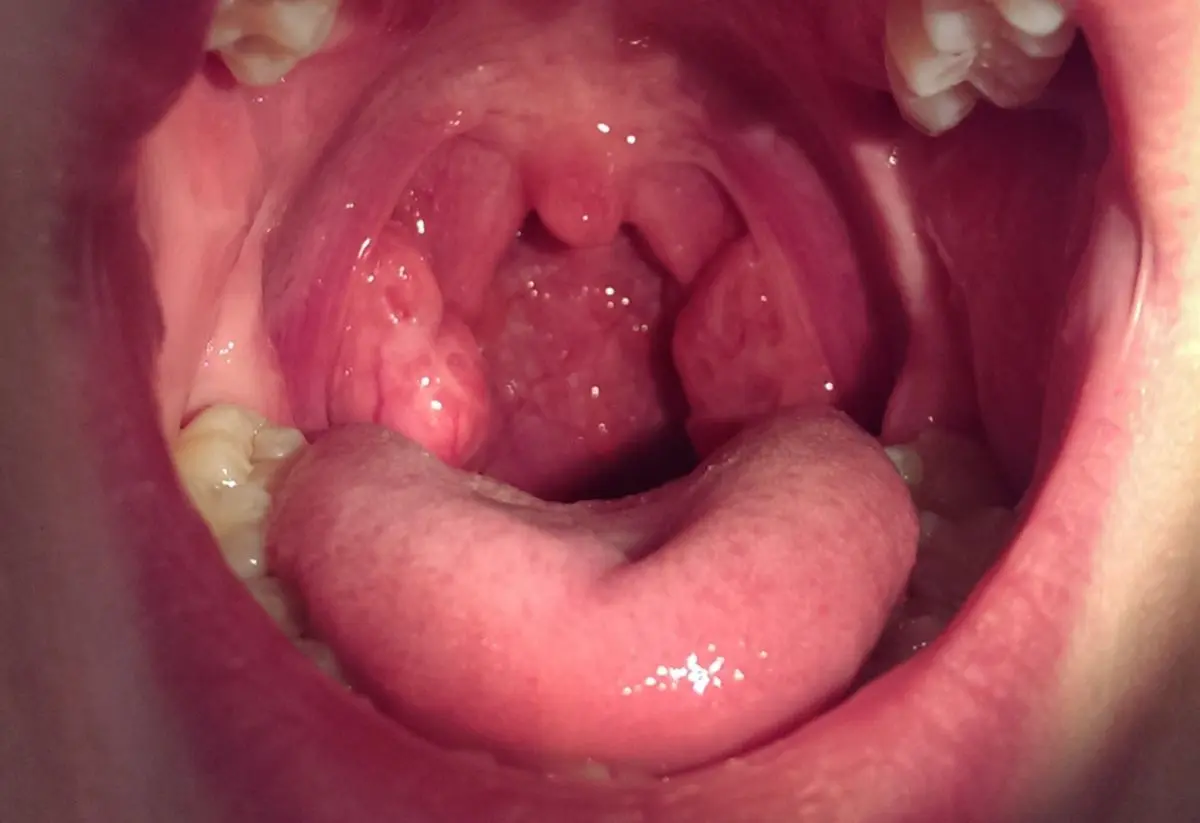

Mandeln sind wichtige Bestandteile des menschlichen Immunsystems und spielen eine wichtige Rolle bei der Abwehr von Infektionen. In den meisten Fällen sind die Mandeln klein und unauffällig. Doch manchmal können sie zu groß werden und zu Beschwerden führen. Dies wird als zu große mandeln bezeichnet, medizinisch als tonsillenhyperplasie .

Zu große Mandeln können zu einer Vielzahl von Symptomen führen, darunter:

• Schwierigkeiten beim Atmen, insbesondere im Schlaf (Schnarchen, Atempausen)

• Schwierigkeiten beim Schlucken

• Häufige Mandelentzündungen (Tonsillitis)